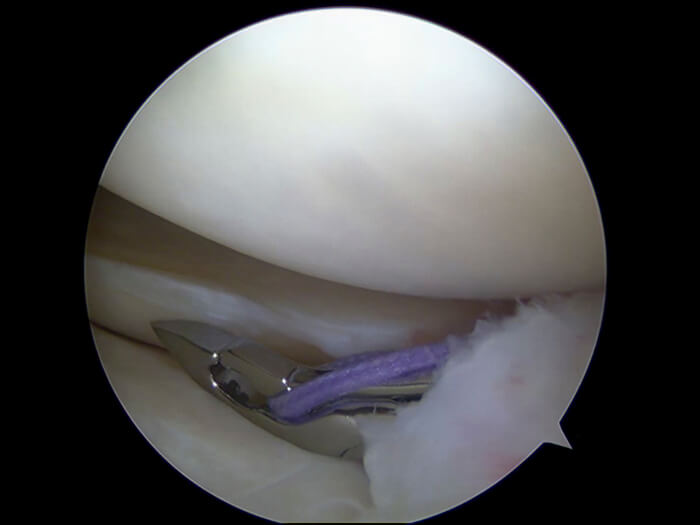

Συρραφή Μηνίσκου

Η λειτουργία των μηνίσκων είναι τεράστιας σημασίας για το γόνατο, καθώς προλαμβάνουν την εμφάνιση οστεοαρθρίτιδας. Έτσι, όπου η ρήξη είναι μικρή και ο μηνίσκος μπορεί να διασωθεί (περιφέρεια - red zone), προτιμάται η συρραφή του, η οποία γίνεται με αρθροσκόπηση. Κατά την αρθροσκόπηση, ο ορθοπαιδικός χειρουργός εισάγει μέσω μιας πολύ μικρής οπής μια ειδική κάμερα και από άλλες εξίσου μικροσκοπικές οπές εισάγει τα εργαλεία του για να συρράψει τον μηνίσκο.

Μηνισκεκτομή

Όταν η ρήξη είναι εκτεταμένη ή πρόκειται για μια παλαιά εκφυλιστική ρήξη, αναγκαστικά προχωρούμε σε μηνισκεκτομή, όπου με τον ίδιο τρόπο αρθροσκοπικά ο χειρουργός αφαιρεί το κατεστραμμένο τμήμα του μηνίσκου, ομαλοποιώντας παράλληλα την υπόλοιπη επιφάνειά του.